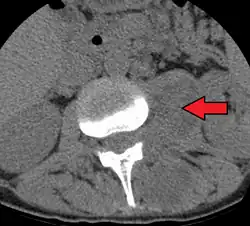

Psoas abscess

| Paraspinal abscess in the psoas muscle | |

Psoas abscess is a collection of pus (abscess) in the iliopsoas muscle compartment.[1][2][3] It can be classified into primary psoas abscess (caused by hematogenous or lymphatic spread of a pathogen) and secondary psoas abscess (resulting from contiguous spread from an adjacent infectious focus).[3]